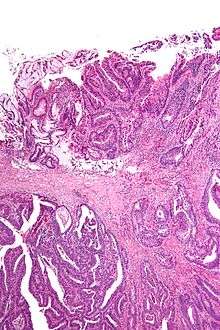

Surgical margin in a surgery report defines the visible margin or free edge of "normal" tissue seen by the surgeon with the naked eye. Surgical margin as read in a pathology report defines the histological measurement of normal or unaffected tissue surrounding the visible tumor under a microscope on a glass mounted histology section.[1][2] A "narrow" surgical margin implies that the tumor exists very close to the surgical margin, and a "wide" surgical margin implies the tumor exists far from the cut edge or the surgical margin. Narrow surgical margin using the bread loafing technique suggests that residual cancer might be left due to false negative error. A surgeon often will perform a second surgery if a narrow surgical margin is noted on a pathology report.

This determination is made with the full understanding of "false negative error" intrinsic in the bread loafing technique of histology (also known as POMA - a term used by the NCCN).[3] The higher the false negative error is, the higher the recurrence rate of a cancer or tumor at the surgical margin. This is due to the misreading of a pathology specimen as being clear of residual tumor, when there is actually residual tumor left where the specimen was not cut and mounted on the histology slide. The "false negative error" is very low in the CCPDMA method of histology processing, and can be very high in the bread loafing (POMA) method of histology processing.[3] In the bread loafing method of processing, one will note a high false negative error rate with narrow surgical margin; and one will note a low false negative error with a wide surgical margin[4] Surgical margin has a much less significant effect on the false negative error rate of CCPDMA methods, allowing the surgeon to routinely use very narrow surgical margins (1 to 2 mm for non-melanoma skin cancer).[4]